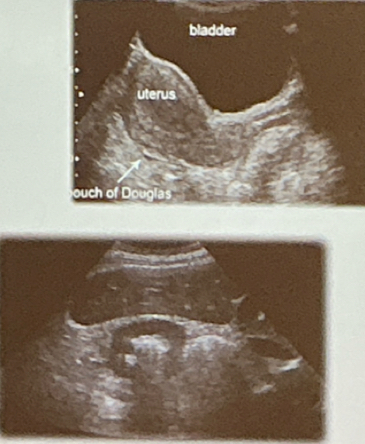

Se coloca encima de la sínfisi del pubis

Evalua Vejiga, espacio rectovesical en el hombre y el fondo de saco de Douglas en la mujer.